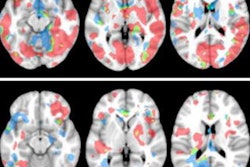

A comparison of DTI scans from the preseason to season's end showed reductions in axial diffusivity among both groups in specific brain regions. Interestingly, however, the high school group "demonstrated greater white-matter microstructure changes than the youth football group, as evidenced by more widespread axial diffusivity reduction," which was contrary to the authors' hypothesis, they noted.

DTI-MR images show white-matter regions with significant preseason to postseason reduction in mean diffusivity (A), axial diffusivity (B), and radial diffusivity (C) among high school football players. Images courtesy of the Clinical Journal of Sport Medicine.After adjusting for the number and severity of head impacts, the researchers found the average reduction in axial diffusivity was significantly greater among high school football players than the younger players -- the high school players had approximately a 2.5% reduction in axial diffusivity, compared with a reduction of 0.4% in the younger athletes (p < 0.05).

The group observed significant reductions among the high school athletes in the corpus callosum, anterior and posterior limbs of the internal capsule, corona radiata, and superior longitudinal fasciculus, among other regions. The junior high school footballers showed significant reduction in more limited regions, including the anterior corona radiata, superior corona radiata, and external capsule.